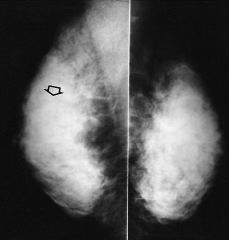

Figs. 5 y 6. Palpación positiva en cuadrante superoexterno de mama derecha (señalamos la zona con flecha hueca). Mamografía: mamas densas levemente asimétricas. Ecografía: masa hipoecoica, ovalada, bien delimitada. Citología: fibroadenoma.

Figs. 7 y 8. Masa dura, supraareolar en mama izquierda (marcamos mama izquierda con flecha hueca). Mamografía: mamas densas sin lesiones aparentes. Ecografía: nódulo irregular, de ecogenicidad mixta y contornos mal definidos. Biopsia: carcinoma ductal infiltrante.